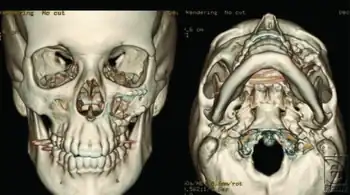

Right zygomaticomaxillary complex fracture with disruption of the lateral orbital wall, orbital floor, zygomatic arch and maxillary sinus.

3-D reconstructions, demonstrating anatomic reduction of the zygomaticomaxillary complex fracture with hardware in place at the infraorbital rim